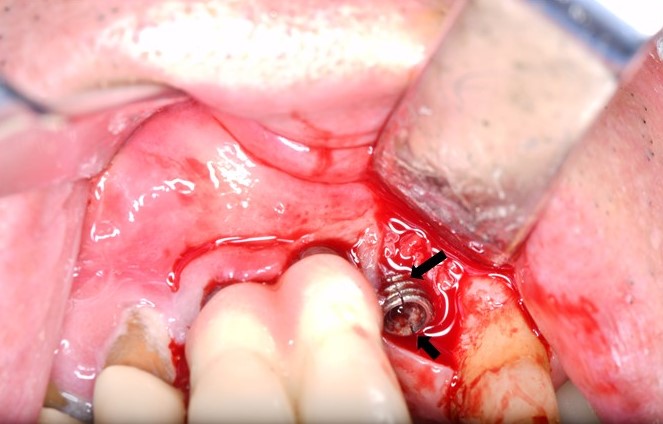

Thirty-three patients with fractured implant fixtures were included in this study. All patients were referred from local dental clinics. Location of the fractured implant, type of implant (external vs internal connection), and possible causes of fracture were investigated. All patients have been described such that identification is not possible directly or through identifiers. Therefore, the Institutional Review Board of Asan medical center exempted this manuscript from approval. All surgeries were performed under local anesthesia (2% lidocaine with 1:100,000 epinephrine; Huons Co., Seoul, Korea) and sedation (Midazolam; Roche, Basel, Switzerland) by one experienced surgeon. Fixtures were removed using a round bur (1.5 mm diameter) and dental elevator. The mesial and distal marginal bone was trimmed, and a dental elevator was inserted between the fractured dental implant and alveolar bone. Every effort was made to preserve the buccal bone to reinstall an implant in the future. Among the 33 patients referred, implant removal and immediate replacement was performed in nine patients, and 24 patients were referred back to the original dental clinic after implant removal. In three cases with large bone defects, socket preservation was performed using Qbonplug® (Inobone Co., Cheonan city, Korea).

This study included 22 men and 11 women (mean age, 60.8 years; range, 33–82 years) with a total of 43 fractured implants (Table 1 and Fig. 1). The incidence of implant fracture was two times higher in men than in women (M:F = 22:11). Among the 33 patients, seven had external-connection implants, of which 12 were fractured (Fig. 2). Internal-connection implants were used in 26 patients, of which 31 were fractured (Fig. 3). Of the 26 patients with internal-connection implants, bone- and tissue-level fractures were observed in 23 and 3 cases, respectively. Maxillary and mandibular implant fracture occurred in 15 and 18 patients, respectively. Single- and multiple-implant fractures were observed in 26 and 7 patients, respectively. Except for two cases of anterior-implant fracture (Cases 9 and 12), all fractured implants were located in the premolar and molar regions (Table 1). In case 10, the fractured posterior single implant was removed through a typical implant removal process and socket preservation was performed using Bonplug® (Inobone Co.) (Fig. 4). Case 12 involved an anterior single-implant fracture with a clear fracture line (Fig. 5). In case 20, multiple fractured posterior implants were removed using an elevator (Fig. 6). In case 22, two fractured posterior implants were removed, and bone grafting was performed (Fig. 7).